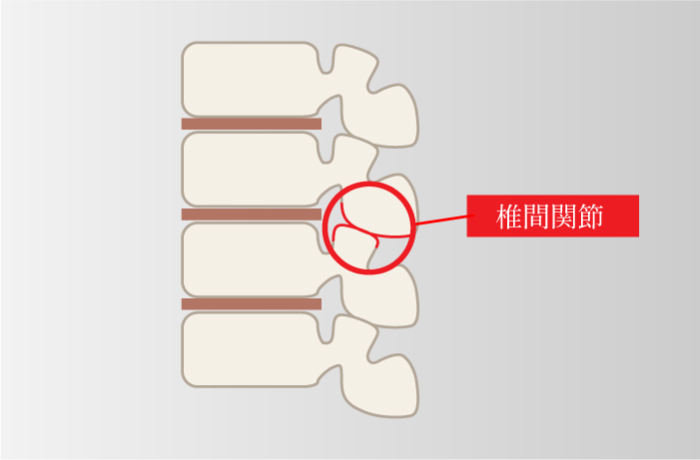

腰を反る動作が原因

-

腰椎が前方にシフトしてしまい椎間関節などに症状がでる。

腰を後ろに反らしたり、仰向けに寝ていると痛みが出ることがある。